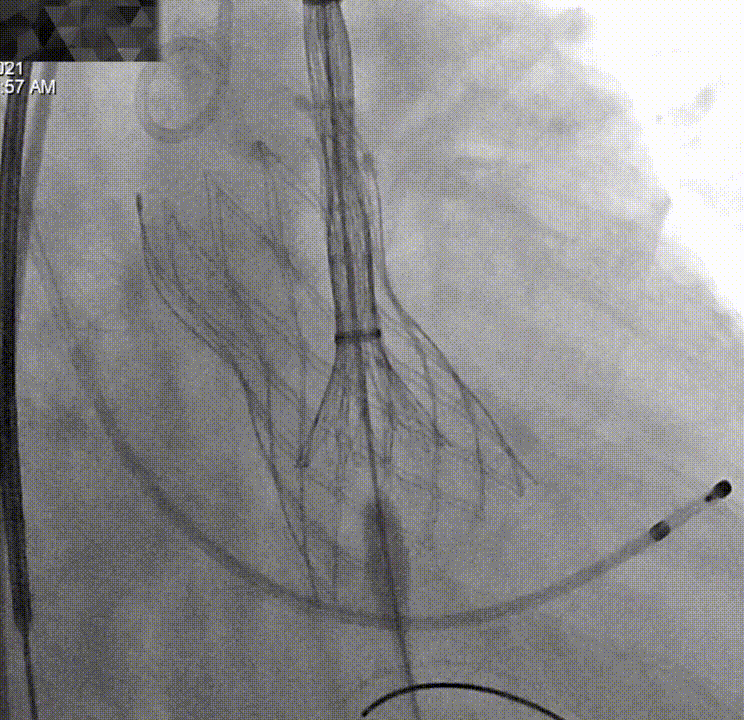

降主血管迂曲,弓部夹角锐利,弓部宽度较短,可谓是“山路十八弯”,得益于TaurusOne®输送系统优异的过弓性能,并在Snare辅助下顺利完成瓣膜系统过弓。

对于单纯返流患者来说,术前也分析了瓣膜移位的风险比较高。结合术前的分析与术中的情况,为保证患者的治疗效果,术中进行了“瓣中瓣”的策略,即第一个瓣膜在非稳定状态下作为锚定骨架,便于第二个瓣膜顺利植入并重建血流动力学。

平行导丝技术第二个瓣膜过弓

第二个瓣膜释放过程